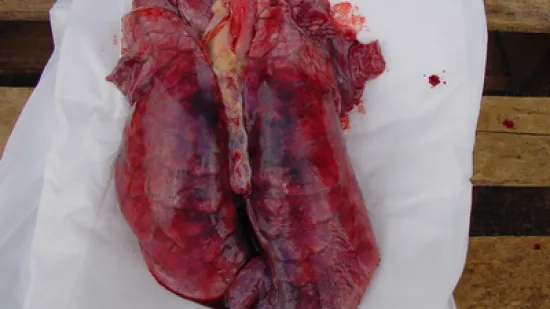

Semaine du 11-Déc-2023

Quelle est la cause la plus probable de cette lésion qui se présente dans >10% des poumons d'un élevage naisseur-engraisseur à l'abattoir ?